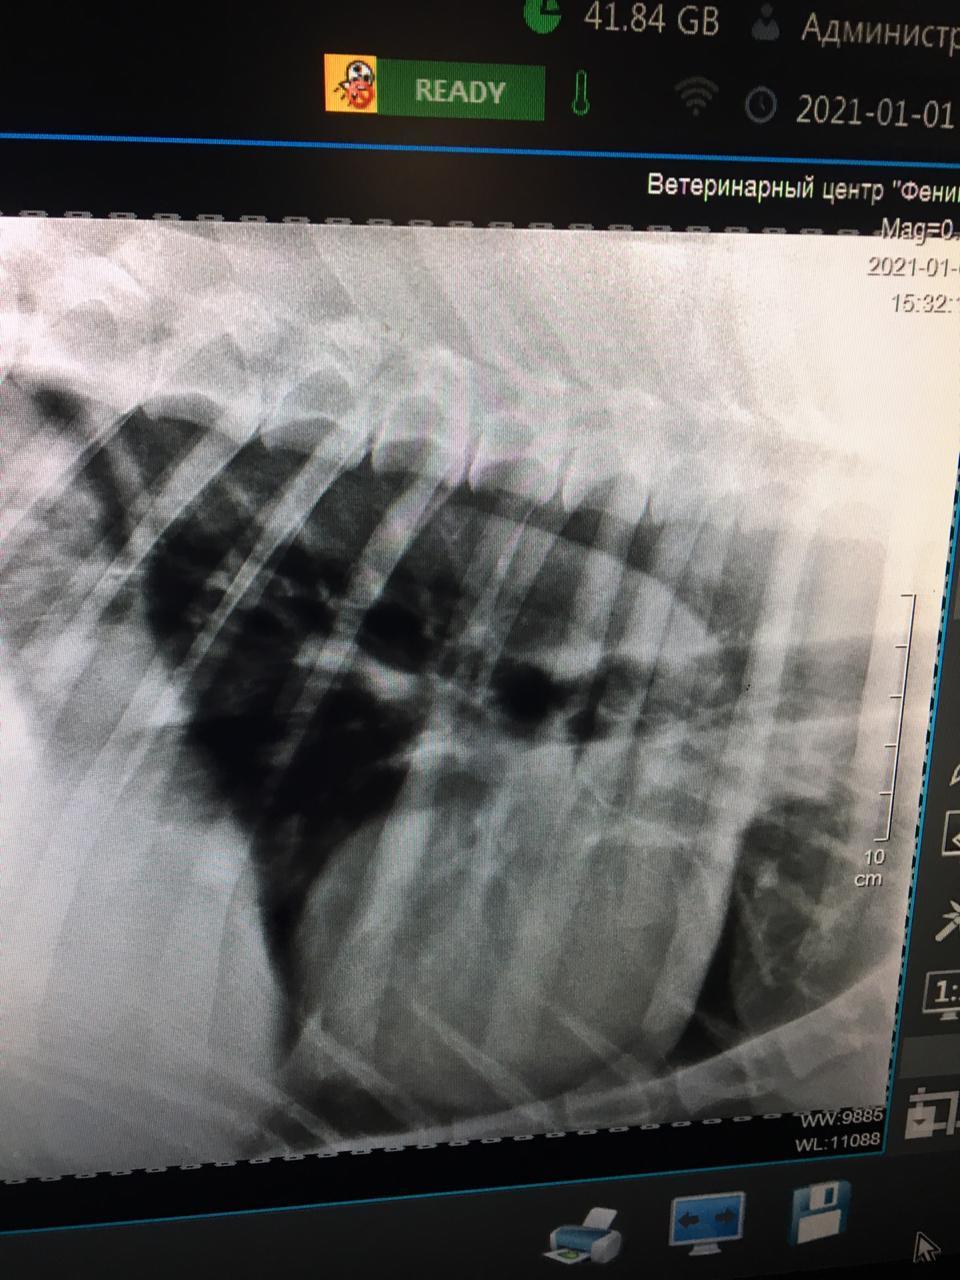

Швы на Умке заживали очень даже не плохо, перевязки и левомеколь с антибиотиками вообще отлично работают :) Он ходил на своей не гнущейся лапе вполне прилично, даже бегать пытался. Химиотерапия прошла без побочек (успели сделать 3 из 4), на рентгене не понятные образования в легких, то ли бронхит, то ли метастазы

Гуляли с ним по деревне нашей в январе, как раз после третьей химии, и что то пискнул он как то не хорошо, но по прежнему шел. Подумали может подвернул как то не удачно ногу или наступил куда. Все осмотрели, все ок. На следующий день, он на ногу не вставал и вообще отказывался ее давать, низ лапы висел как тряпочка. Что то опять пошло не так. Сделали рентген, который показал, что протез сломался внутри, там, где основная часть крепится к лапе. Если услышите что титан крепкий металл, можете посмеяться. Позвонили хирургу, он назначил операцию через неделю. Было понятно, что заменять всю конструкцию нет смысла, надо отрезать низ лапы и придумывать что то на это место. Я очень переживала за Умку и написала врачу, что неделя без возможности ходить, и когда так больно, это вечность. Что я не ору и не ругаюсь, что титан поломался, и вообще максимально лояльна ко всем, но собаке осталось не долго, давайте побыстрее его прооперируем. Короче, на следующий день я поехала с ним на операцию.

Место, где не выдержал титан.